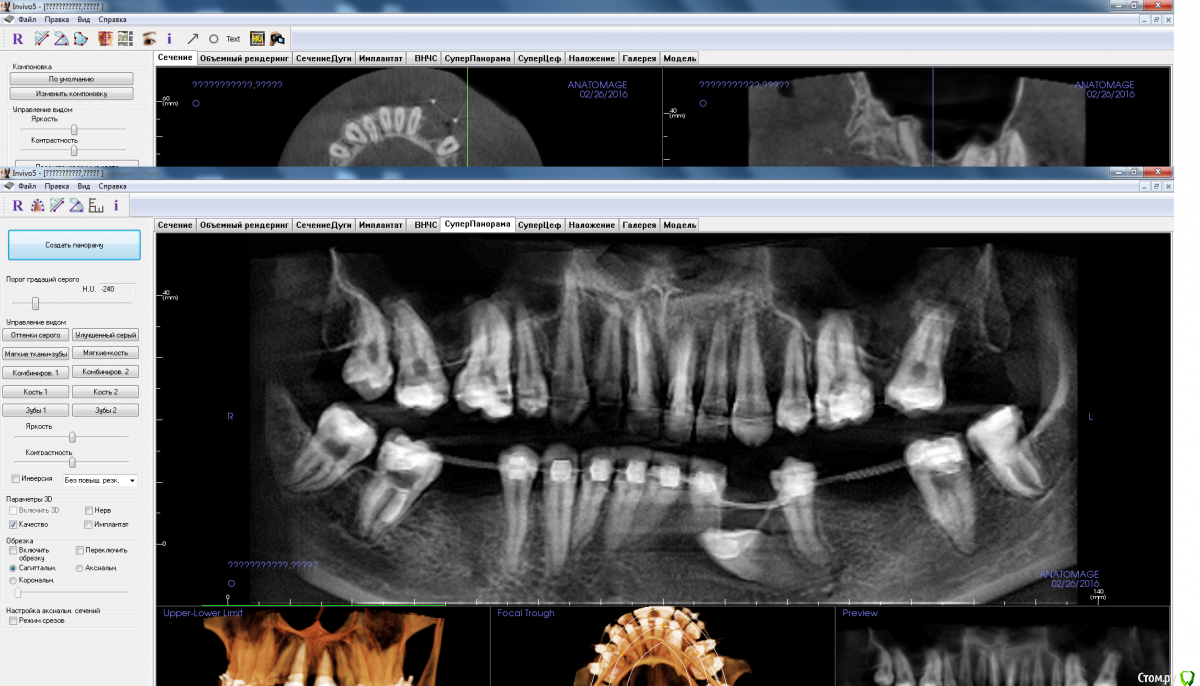

adamskot Опубликовано 8 апреля, 2016 Поделиться Опубликовано 8 апреля, 2016 Коллеги, доброго времени суток.Ретенированный клык уже удален,на его место биоосс и мембрана.Кто как бы поступил в третьем сегменте? заранее спасибо за мнения) Ссылка на комментарий

Fibez Опубликовано 8 апреля, 2016 Поделиться Опубликовано 8 апреля, 2016 Ред_бутлер, там же всего 10 мм от края гребня до канала? Куда заглубляться-то? Или ставить 3,5х8мм? Ссылка на комментарий

Aquarius Опубликовано 8 апреля, 2016 Поделиться Опубликовано 8 апреля, 2016 8,5 вполне себе рабочий размер Ссылка на комментарий

red_butler Опубликовано 8 апреля, 2016 Поделиться Опубликовано 8 апреля, 2016 Ред_бутлер, там же всего 10 мм от края гребня до канала? Куда заглубляться-то? Или ставить 3,5х8мм?С чего Вы взяли, конечно выставленные скрины полной информации не дают, но мне видятся 12-14 мм Ссылка на комментарий